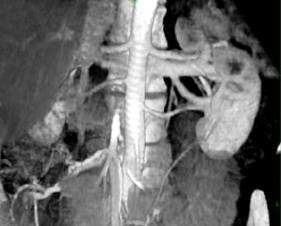

Cea mai comuna anomalie a sistemului venos stang este vena renala circumaortica, observata la aproximativ 15% din pacienti. Vena renala stanga se bifurca intr-un brat ventral si unul dorsal, care inconjoara aorta abdominala. Mai putin frecventa este vena renala stanga retroaortica, intalnita in proportie de 4%. In acest caz, vena renala stanga se varsa in portiunea lombara inferioara a venei cave inferioare. Pot fi observate si vene renale accesorii (pana la 15% din pacienti).

Imagine 3D anterioara la un pacient donator arata prezenta unei artere renale unice (sageata) si a doua vene renale drepte (varfuri de sageti).

AngioCT este foarte potrivita si pentru evaluarea rinichiului post-transplant. O complicatie relativ frecventa dupa transplant este stenoza de artera renala, raportata la 3-15% din pacienti, in primii 3 ani post-transplant. Ea poate sa evidentieze neinvaziv pediculul rinichiului transplantat, permitand diagnosticarea stenozei. Ocazional, clipsurile chirurgicale pot da artefacte in apropierea arterei transplantate, limitand astfel evaluarea acesteia.

Stenoza de artera renala este importanta daca reprezinta o etiologie potentiala reversibila pentru hipertensiunea arteriala. Apare la mai putin de 5% din adultii hipertensivi. AngioCT reprezinta o metoda buna si neinvaziva de screening pentru diagnosticarea stenozei de artera renala, cu acuratete de pana la 96%. Este de asemenea foarte sensibila si specifica pentru demonstrarea ocluziei de artera renala. Imaginile axiale nu sunt suficiente pentru evaluarea stenozei deoarece arterele renale au deseori un traiect variabil si sinuos. Dar angioCT permite observarea arterelor renale in multiple planuri. In caz de calcificari extensive, sunt foarte utile imaginile 3D si cele angioscopice. Ea poate evidentia si semne secundare de stenoza de artera renala, incluzand dilatatii poststenotice si modificari de parenchim renal de tip atrofie si scadere a volumului corticalei. Este de asemenea foarte utila in evaluarea post tratament a grefelor renale si poate face diferenta intre materialul grefei si substanta de contrast intraluminala.

Embolia tumorala este o indicatie uzuala pentru evaluarea pediculului renal. Invazia tumorala a venei renale este cruciala in precizarea posibilitatilor chirurgicale de indepartare a unei tumori renale. Venele renale sunt foarte bine vizualizate pe angiografia CT in faza corticomedulara sau arteriala. Opacifierea completa a VCI de obicei necesita o achizitie secundara helicoidala la 90-120 de secunde post-injectare. Dilatatia venei renale stangi datorita unui sunt spontat splenorenal la pacientii cu hipertensiune portala poate fi de asemenea diagnosticata.

Se pot observa si anevrismele si disectiile de artere renale, angioCT definind cu exactitate extinderea si localizarea acestora. Angiografia computerizata nu evidentiaza numai anatomia vasculara renala, ci si modificarile parenchimatoase secundare, incluzand infarcte si atrofii. Anevrismele pot fi izolate sau in cadrul unei vasculite sistemice. Calcificarile pot obstrua imaginea unor anevrisme, in acest caz foarte utile fiind imaginile tridimensionale.